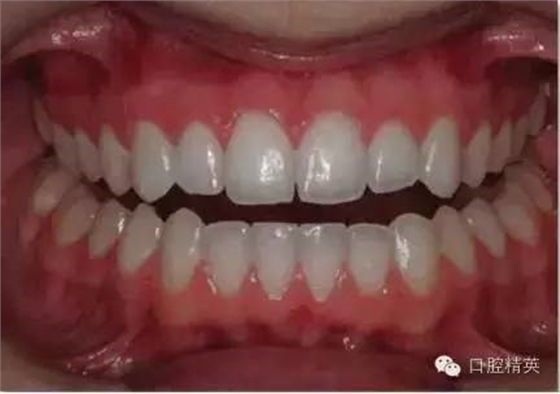

大笑照

正面观

1:2 (1:3)放大倍率

无需使用拉钩

• 自然大笑,记录此状态下露出的最多牙齿数目及露龈情况。面部其他肌肉应为放松状态。

•照片的纵向中心应为上唇人中交接点。

•不要主动移动相机补偿中线不齐的问题。

•上颌牙齿的切缘平面应为相片的水平中线。如果患者的切缘平面在正面照中为倾斜的,此照片应如实记录,而不要旋转相机补偿牙齿的倾斜角度。

•应位于患者正前方拍照

•避免相机与牙齿形成角度引起切平面的问题。相机应与对象的纵向和横向均成90°角,以避免切平面倾斜的问题。

•使用1:2 (1:3)放大倍率,患者的嘴唇应全部位于画面内。请注意下颌牙齿不一定能在此时露出。

•在中切牙及侧切牙处对焦。选取适当的景深(通过高F值获得)使得尽可能多的牙齿在焦距内。

•此照片无需设置背景。